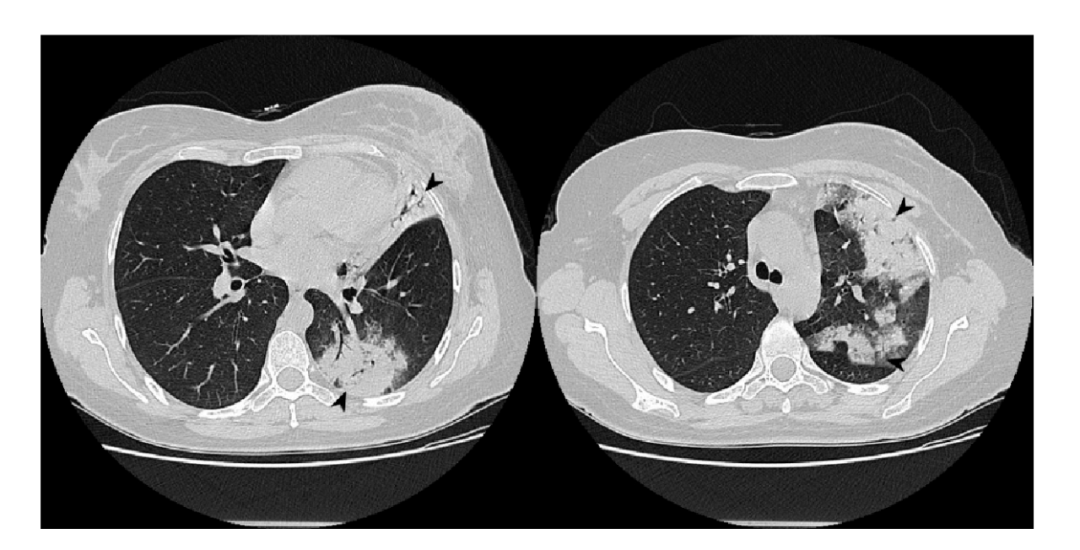

2. 影像学表现

①肺实变磨玻璃密度影;②小叶周围阴影;③环礁征;④结节或肿块;⑤小叶间隔增厚;⑥束状或条带阴影;⑦进行性纤维化。

图片

隐源性机化性肺炎主要的影像学表现

图片来源:Diagnostics (Basel), 2020, 10(5):262.

分布于周围的多灶性和非对称实变

外周性实性结节:

小叶周围型:

线状和带状影:

环礁征—磨玻璃影:

进行性纤维化:

3. 影像学特点

(1)典型影像:斑片状肺泡浸润影(典型COP)。

(2)不常见影像:孤立性阴影(局灶性COP);浸润性阴影(浸润性COP)。

(3)少见影像:反晕轮征;进行性肺纤维化并网格及实变;多发性结节;支气管中央型实变;不规则线或带状影;小叶周围型阴影。